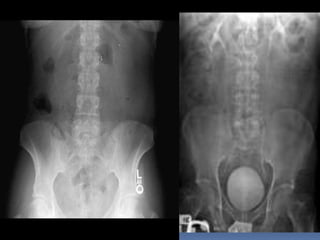

PROYECCION SIMPLE DE

ABDOMEN

CRITERIOS DE EVALUACION

P.S.A.

 Apreciar desde el

abdomen superior hasta

la sínfisis del pubis.

 Lumbares, pelvis y

ultimas costillas sin

rotación.

 Apófisis espinosas en el

centro de cuerpos

vertebrales.

 Ver el bazo, riñones,

psoas y “borde inferior

hepático

INTERPRETACION

 Estructuras óseas

(densidades).

 Tejido blando

 Psoas.

 Bazo

 Niveles Hidroareos.

 I.D.

 Colon

 Silueta Renal